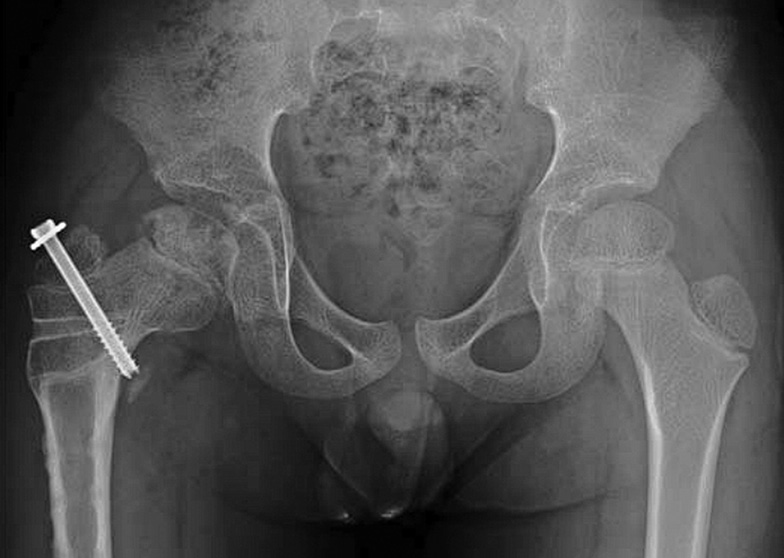

In 2011. McGillion and Clarke developed additional radiological criteria to the existing ones to objectify the indications for epiphysiodesis [21–23]. They defined the following radiographic criteria to evaluate epiphyseal displacement in necrosis on anteroposterior pelvic radiographs: the angle between the Hilgenreiner line and line along the edges of the epiphysis of the femoral head. A change in the angle between these lines indicates displacement of the femoral head in relation to the pelvis, which makes it possible to suspect aseptic necrosis and deformation of the lateral growth zone over time. The authors do not give the normal values of this angle; however, note that in the norm, this angle is positive (>0), and in pathology, it decreases and the lines become parallel (Fig. 2).

Fig. 2. Determination of the tilt angle [24]

This criterion is called the “tilt angle.” When evaluating postoperative radiographs and following up with patients, the change in this angle allows us to assess the dynamics of the effect on the growth zone and the degree of correction of the deformity, which is what the authors presented in their study. However, they noted that the “tilt angle” is a two-dimensional analysis, whereas CT scans can assess the magnitude of anteversion in addition to the valgus deformity. CT further showed that the bony bridge of the disturbed growth zone can be located in both the posterolateral and anterolateral parts of the epiphysis of the head. Thus, the concomitant torsional deformity of the femur complicates the prediction of the efficacy of medial epiphysiodesis, and a more thorough examination of the patient is required [24].